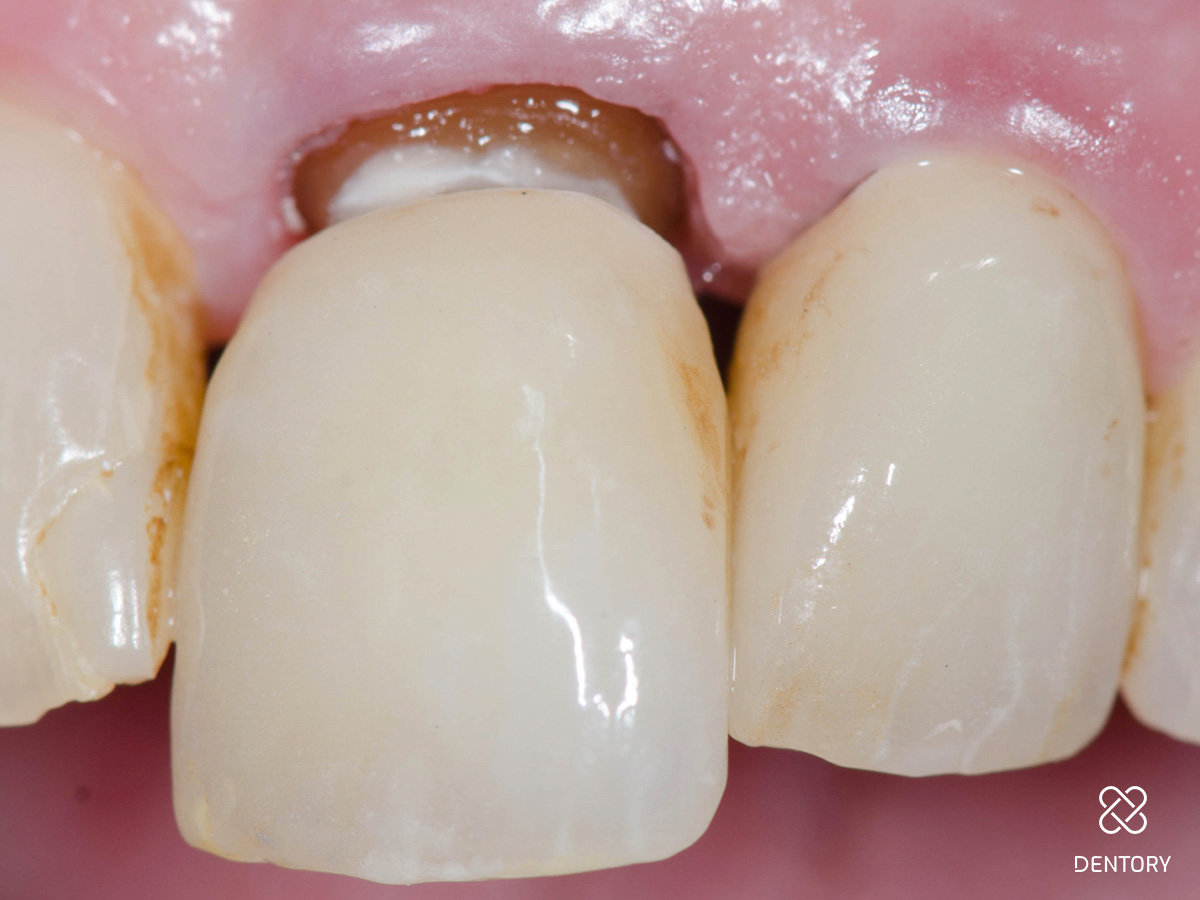

Abbildung 6

Einprobe an 21: Die Einprobe der Krone 21. Die Kronen werden auf Farbe, Form und Passgenauigkeit überprüft.